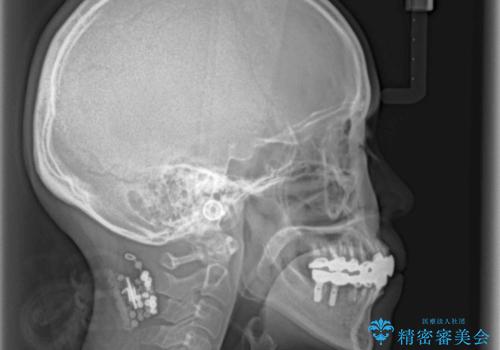

- 下顎の前歯に激痛を覚えて来院された患者様です。

取り急ぎ下顎前歯数歯の根管治療を、銀座しらゆり歯科医院長の林先生にお願いし、それ以外に気になっている、不自然な色調のクラウン、金属部分が見えてブラッシングがしにくいインプラント補綴、口元の突出感、出血のしやすい歯周ポケットなど、全てを解決するための治療を行うこととしました。